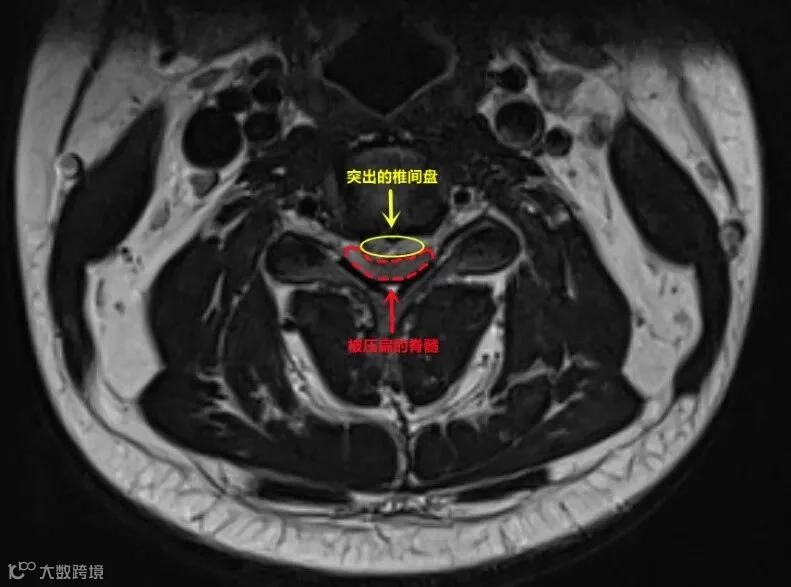

小何(化名)是深圳某公司的职员,从事外贸出口工作,常年要在电脑前工作,颈部、背部等局部肌肉长期紧张、劳损。偶尔劳累后,肩膀脖子都会酸胀。

几次按摩之后,小何渐渐感觉右半边身子有点儿“钝”,等赶到深圳大学总医院,小何的整个右边身子已经“瘫”了。经过医生治疗后康复。